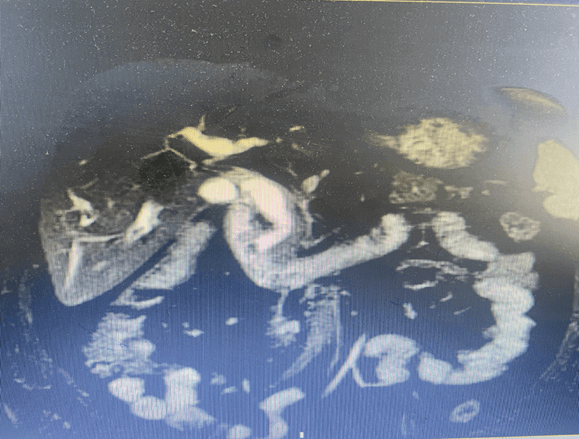

胆总管结石,传统治疗方法常需切除胆囊并切开胆总管,创伤大、恢复慢。如今,经胆囊管胆总管结石胆道镜取石术 提供了更为精妙的微创解决方案。

该技术充分利用胆囊管这一天然通道。手术中,医生在腹腔镜下,将纤细的胆道镜经胆囊管插入胆总管,如同配备高清探头的“精工镊子”,在直视下精准定位结石,并利用网篮等器械将其完整取出。